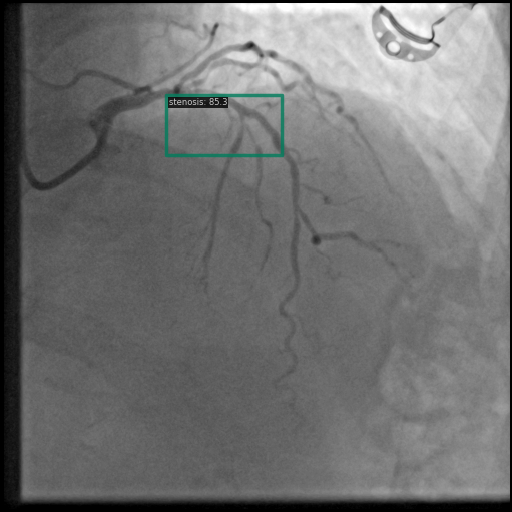

Figure 1 shows sample images from the ARCADE dataset with annotations for stenosis detection. The annotations highlight regions of arterial narrowing, providing ground truth data for training and evaluating object detection models.

To further assess the detection performance, qualitative results for three test images are presented in Figure 2. The first column shows the original images with ground truth annotations. The second, third, and fourth columns depict detections from DINO-DETR, Grounding DINO, and YOLO, respectively.

(a) Original (b) DINO-DETR (c) Grounding DINO (d) YOLO

The qualitative comparison in Figure 2 reinforces the trends observed in the quantitative evaluation. DINO-DETR produced fewer detections, occasionally missing relevant stenotic regions, consistent with its conservative detection strategy aimed at minimizing false positives [6]. Grounding DINO, although capable of identifying more regions, sometimes resulted in cluttered predictions due to over-detections [7]. YOLO provided a reasonable trade-off by effectively capturing anatomical structures while maintaining relatively high confidence scores and clear visualizations [5].